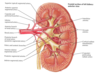

venous drainage of kidney

R & L renal V

- anterior to A

- L receives L suprarenal and L gonadal

drain to IVC

L passes anterior to aorta, posterior to desc SMA